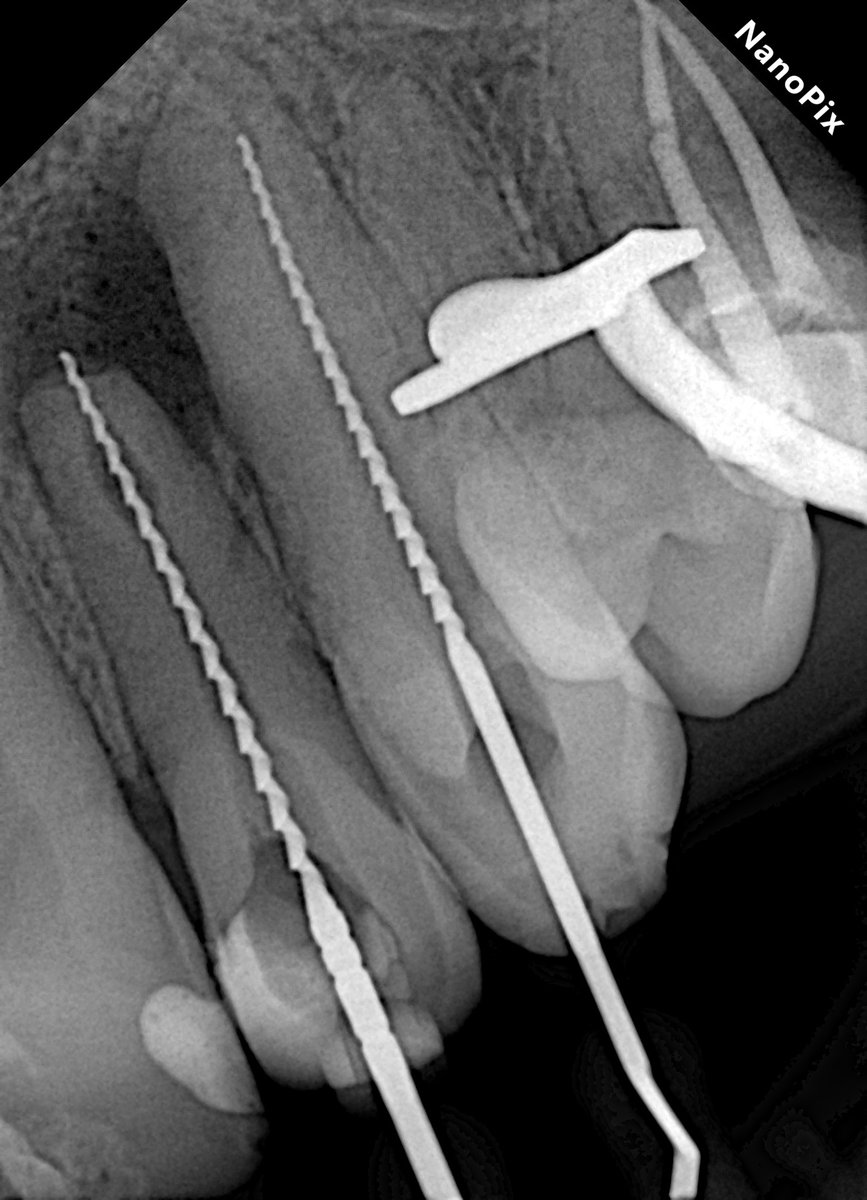

Предсказать реальную глубину процесса сложно, даже по кт. Если полость отчётливо видна уже на рентгене, то ничего хорошего ждать не стоит. Но зуб - это живая единица, и при длительном процессе полость нерва изменяет свою анатомию и "прячется" глубже.

То есть, вырабатывается вторичный дентин, который защищает зуб от процесса. И вроде бы, согласно анатомии, этот самый процесс уже должен был давно вскрыть полость нерва, но нет - иногда оказывается, что это лишь глубокий кариес.

И бывает абсолютно наоборот, когда работаешь с кариесом на контакте (например, в случае с премолярами), то вскрываешь полость нерва практически сразу - это максимально обидно.

Во всех остальных случаях только препарирование зуба различными вариациями бормашины. На данный момент это всегда происходит под анестезией. Пациент не ощущает боли от слова совсем, за некоторыми исключениями, которые корректируются.

Само препарирование происходит с подачей воздуха и водяного охлаждения для избежания перегрева твердых тканей и профилактики ожога. Плюс большая часть стоматологов использует изоляцию - коффердам, который позволяет повысить комфорт всем.